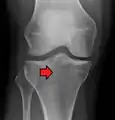

Lateral Tibial Plateau fracture XRay with Depression

• Type III: Focal depression of articular surface with no associated split.